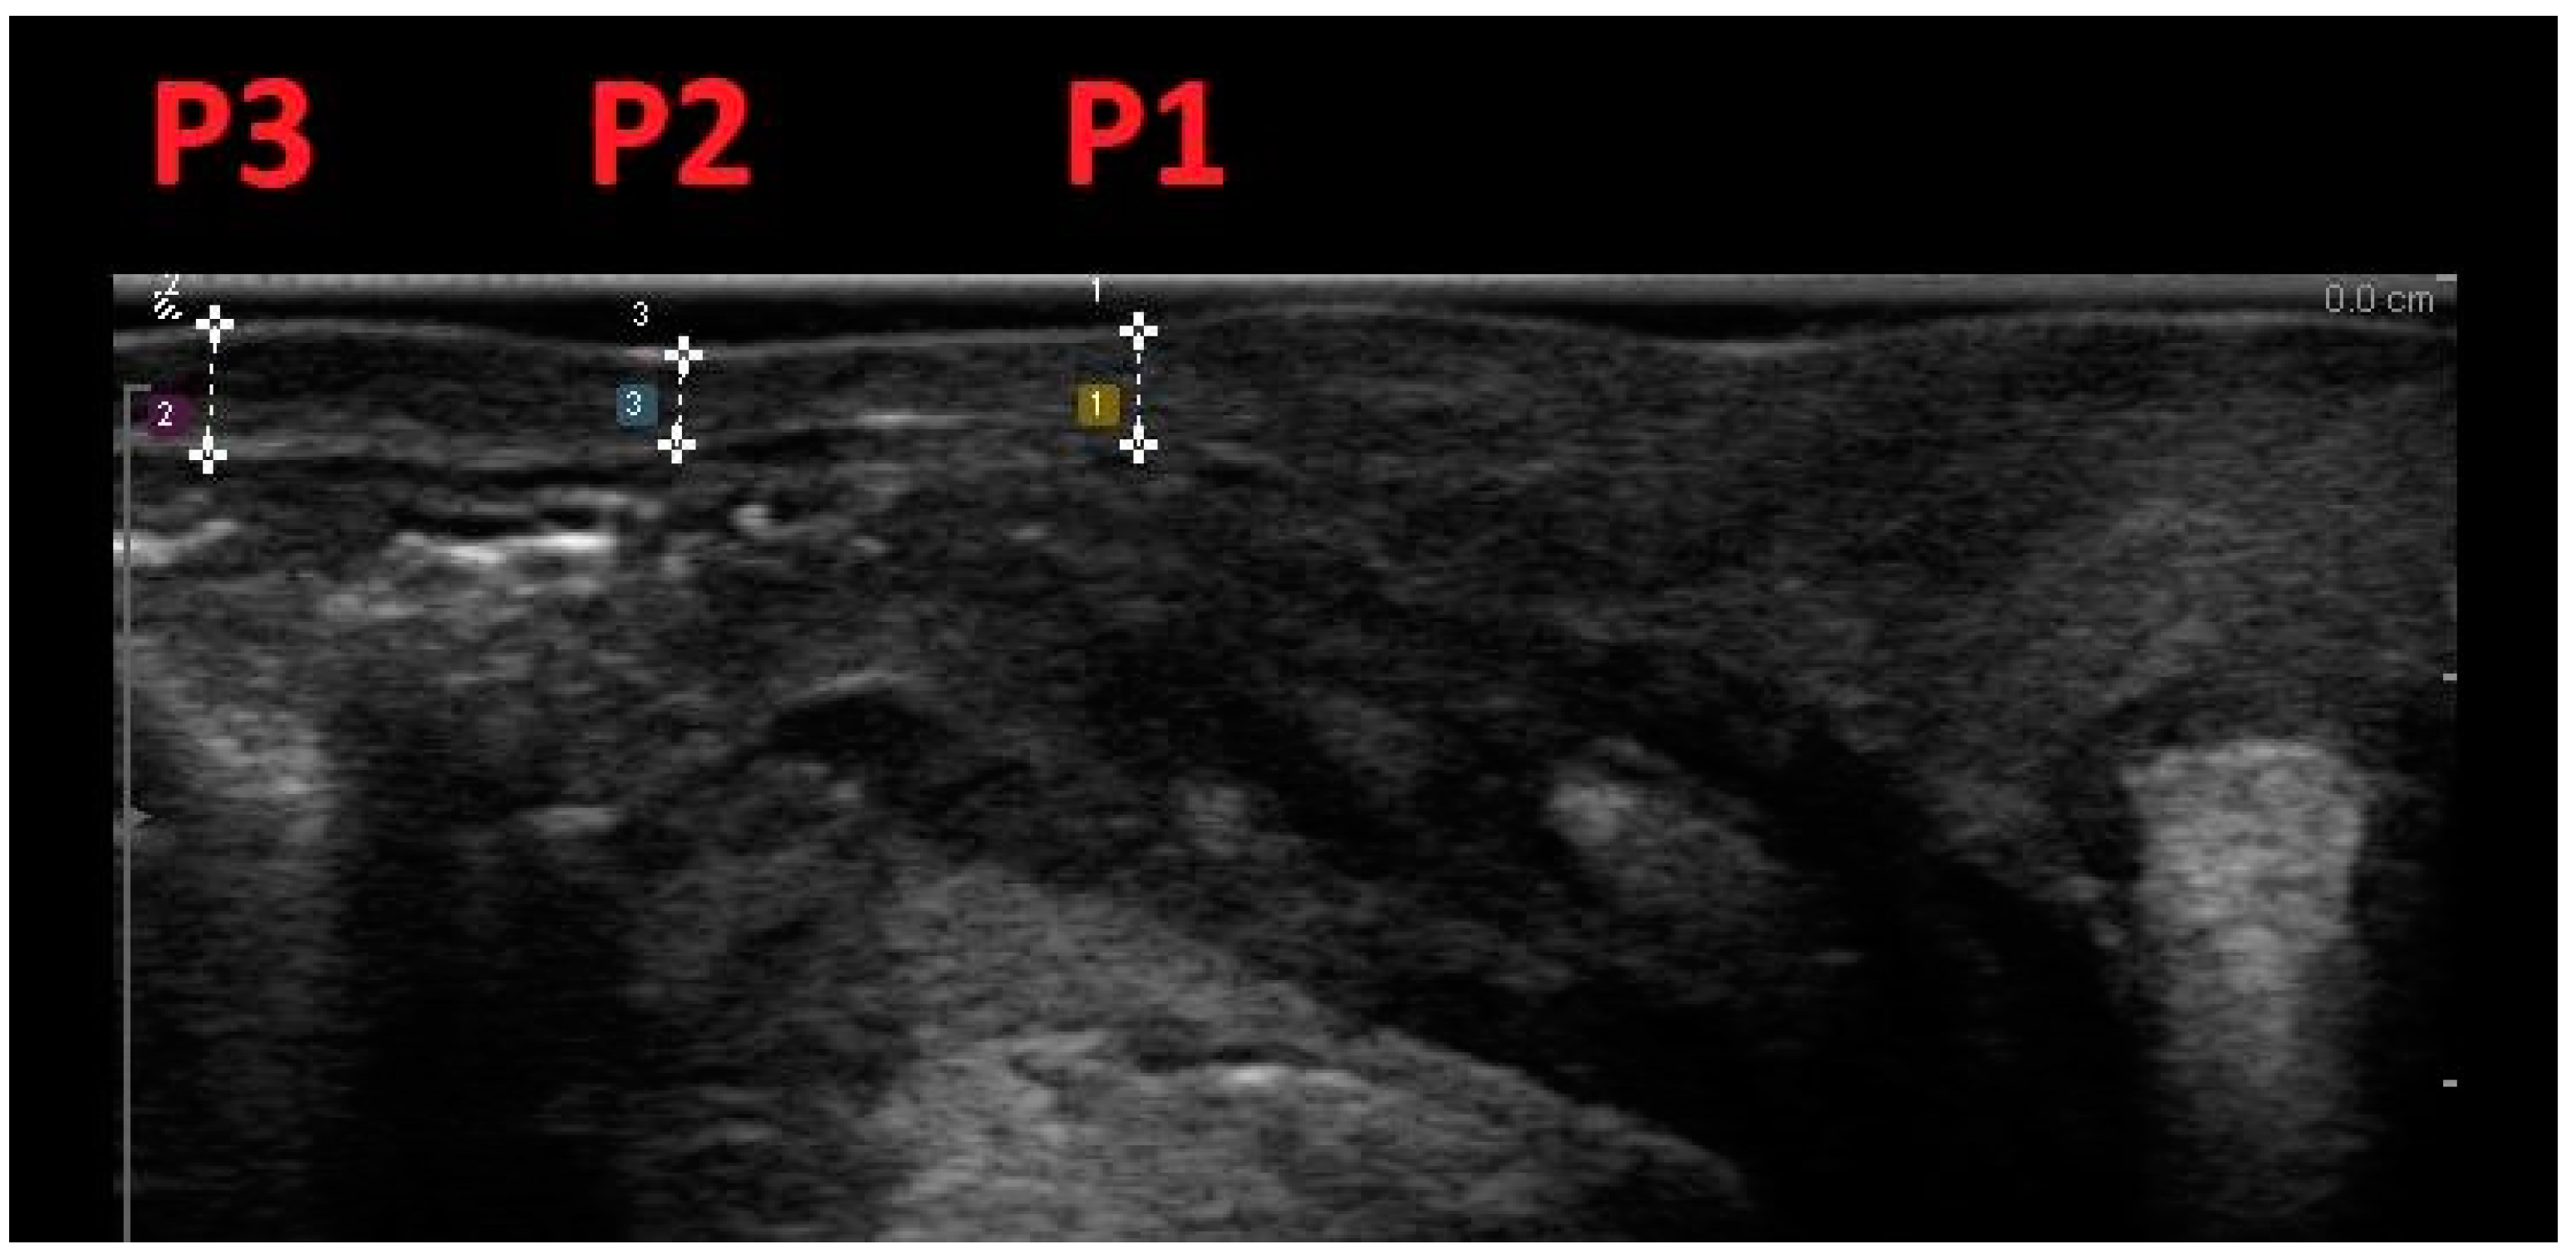

| P1 | 2.8 (1.95) | 3.4 (1.94) | −0.06 | 0.19 | −0.47/0.34 | 0.952 |

| P2 | 3.0 (1.26) | 2.8 (1.23) | 0.05 | 0.08 | −0.14/0.23 | 0.975 |

| P3 | 2.3 (1.46) | 2.7 (1.62) | 0.18 | 0.12 | −0.09/0.46 | 0.974 |